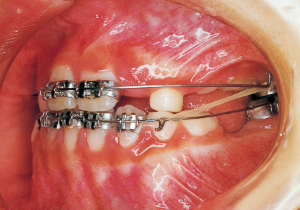

7 1-22-’80 Beginning of first phase

Aware that treatment would be challenging, we proceeded with the first phase of treatment based on the current functional status and anticipated developmental implications (7). During the mixed dentition phase, the body responds readily to treatment, allowing for relatively rapid tooth movement and changes in jaw position (8,9). Subsequently, once freed from mechanical stimulation, growth continues according to inherent predispositions, often appearing to disregard occlusal functional efficiency (10,11). These changes are clearly observable on cephalometric radiographs (12). After confirming the extent and direction of growth, we decided to incorporate surgical intervention into the treatment plan and wait until the age when growth begin to decline.